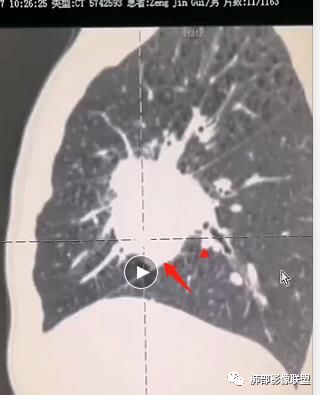

对,有血管走形

这个血管在病灶中间走行。鳞癌不会这样的。

是两个病灶连到一起了,还是一个病灶两个成分?

我认为还是一个

影像表现缺乏特异性,CT最常见的表现是位于周围肺野的实质性肿块,病变部位以上叶多见,常位于胸膜下;

因为病灶有上皮成分和间叶成分,所以兼具肺癌和肺肉瘤的影像学特征,

1.具有肉瘤的特性:肿瘤体积一般较大,直径约大于5cm,边缘清楚、光整,由于肿瘤生长迅速,可见大片坏死,坏死边界清楚;常见支气管推移。

2.具有癌些特性:如分叶、短毛刺、空洞,但是钙化及胸膜凹陷征少见,病灶往往是直接侵犯胸膜,可以远处转移,肺门及纵隔淋巴结可明显肿大;

3.强化方式:增强后病灶以环状强化为主,病灶周边多以癌组织为主,血供丰富,病灶中心区则以肉瘤成分为主,血供较差,易出现粘液样变性、坏死、出血,坏死边界清楚,所以增强CT对PSC与普通型肺癌有一定的鉴别价值。

(中央型PSC肿块常位于肺门处,肿块多较大,边界较光整,伴有阻塞性肺炎或肺不张,与常见类型肺癌不易鉴别。)

病例小结

1.本病例结合病理结果及影像综合分析,应该符合肉瘤样癌,上皮成分是腺癌为主;肿块的边缘毛刺、分叶及周围癌型淋巴管炎征象有符合腺癌的影像表现之处。

2.肿块巨大局部边缘膨隆、光整,坏死较彻底;明显跨叶生长(途经发育不全叶间裂或肺门,注意患者没有胸水),支气管阻塞伴推移等,这些更符合肉瘤的特性。

3.坏死区边界较清楚(皮囊样),环形强化明显,病灶内血管穿行等,都不符合我们常见的鳞癌。

4.肺肉瘤虽然也是肿块巨大,呈大片状坏死,但是边缘光整圆隆,没有分叶、毛刺征象,较少出现肺门及纵隔淋巴结转移。